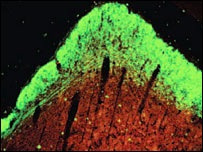

Nerve growth (shown in green) occurred after the injections